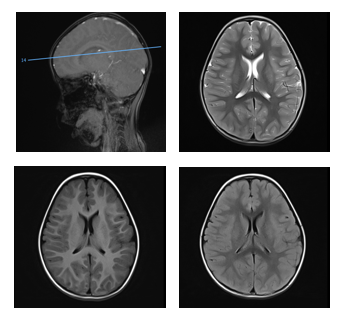

补液治疗时,晓月渐渐出现嗜睡、意识模糊、双眼上翻凝视等症状,最后竟然陷入昏迷。紧急抢救后,她被送入重症监护室(PICU)。检查发现,她急性酒精中毒,出现了严重代谢性酸中毒、大脑功能受损。

检查发现,晓月出现了颅内多发病变。监测生命体征、上呼吸机、降颅压、扩容补液……一番忙碌后,晓月终于“缓”了过来。